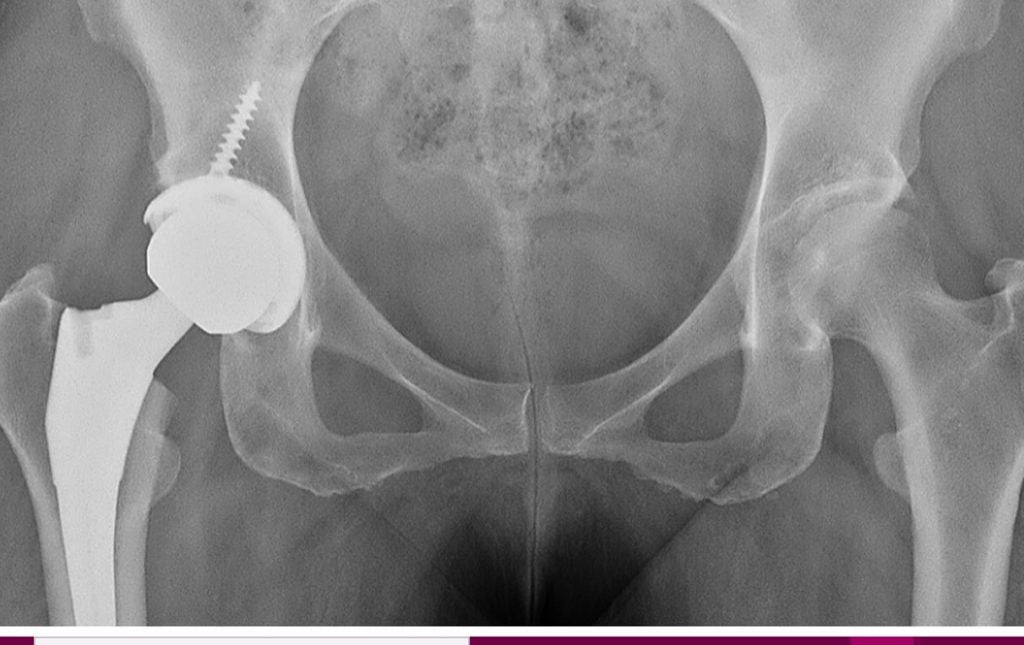

Hip Arthritis

Brian P. Chalmers, MD

Hip and Knee Replacement Surgeon